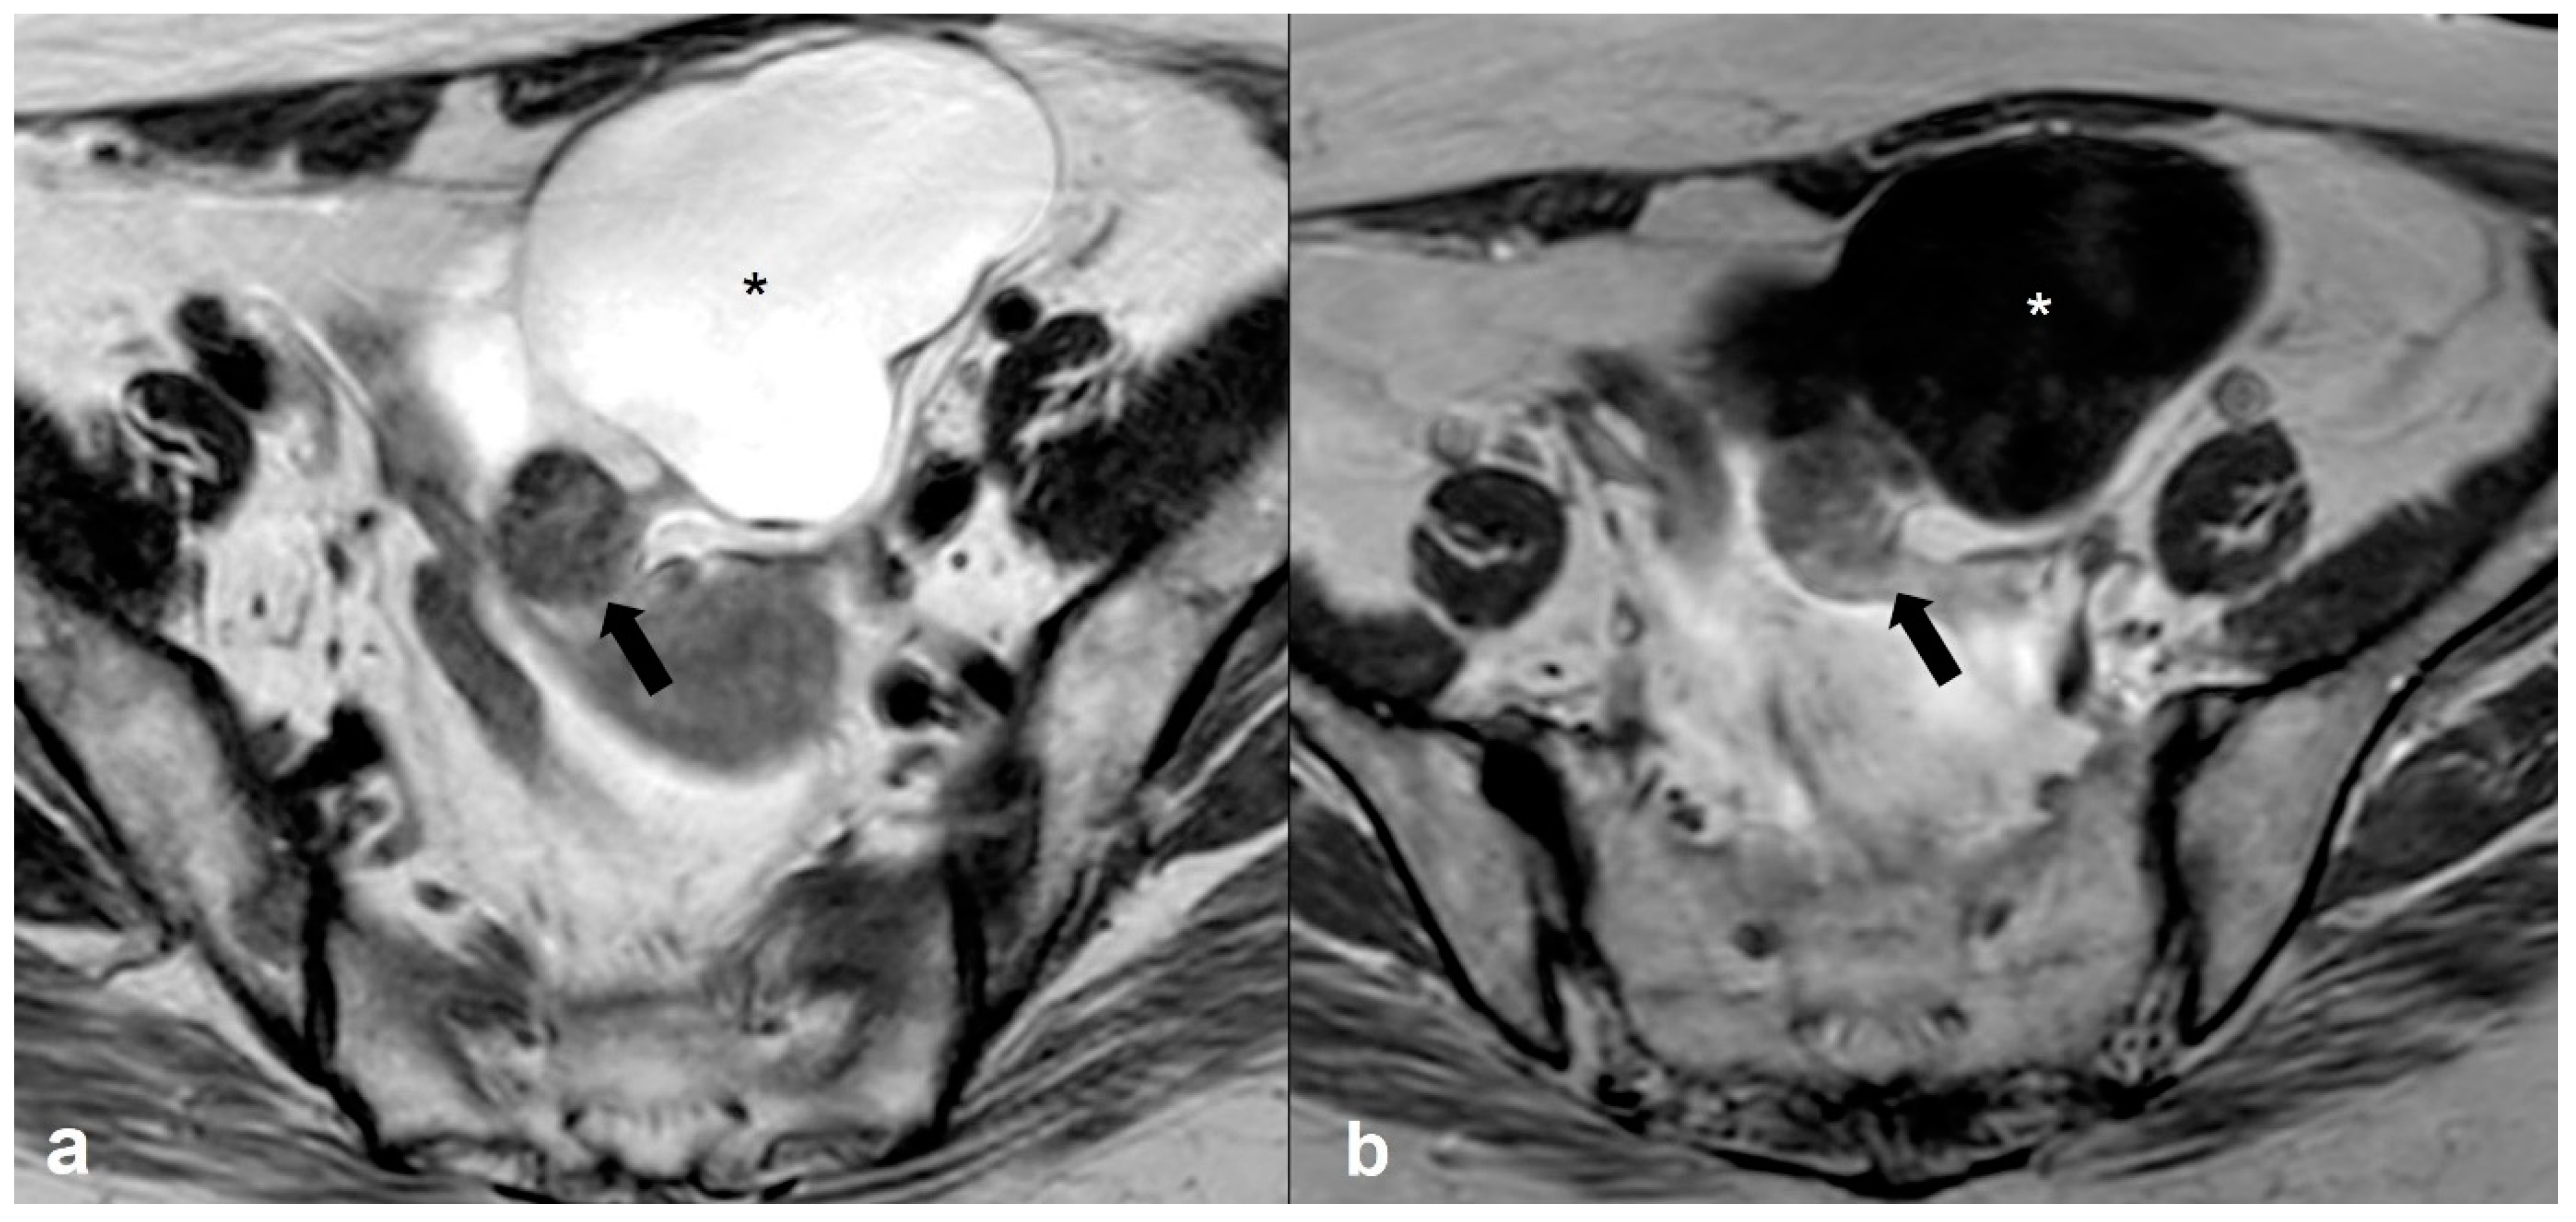

2.3.5. Metastases